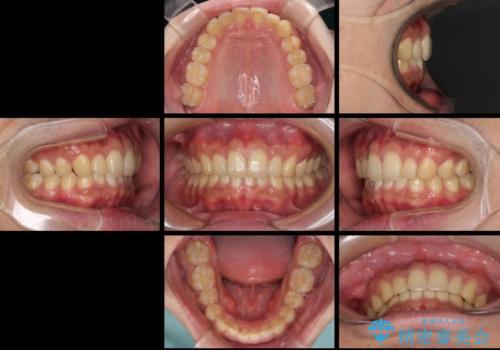

- 上下前歯のデコボコと下の前歯が隠れるほどの深い咬み合わせを気にして来院された患者様です。

インビザラインによる上下歯列の拡大と、IPR(歯と歯の間を削る)にるスペースの獲得により、口元のデコボコとディープバイトを改善することとしました。

デコボコがなくなったことで日頃の清掃が行いやすくなり、深い咬み合わせが改善したことで、食いしばりによる顎の負担も軽減されました。